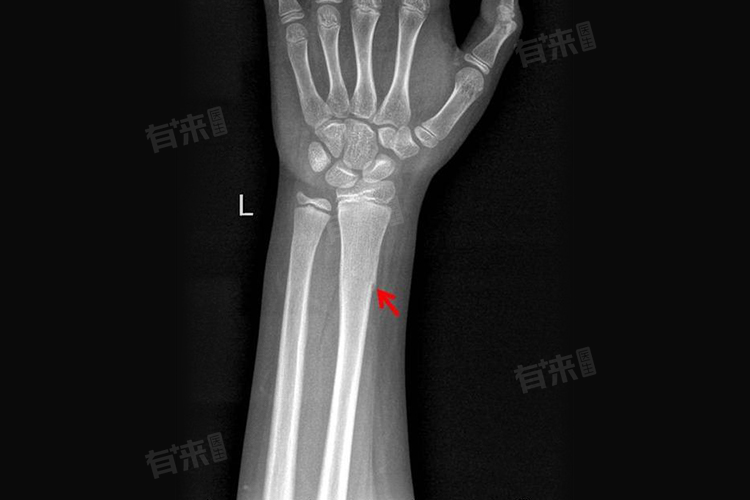

1、骨折部位:不同部位的骨折,骨折线消失的时间存在差异,如上肢的骨折,如桡骨骨折,骨痂形成后可能在3-6个月骨折线开始逐渐模糊并消失,而下肢的骨折,如胫骨骨折,由于承受的压力较大,骨折线消失的时间可能会延长,大概在4-8个月甚至更久。

2、骨折严重程度:骨折的严重程度对骨折线消失的时间有显著影响,如果是简单的骨折,骨痂形成后,骨折线可能在相对较短的时间内消失,一般轻度骨折可能在4-6个月骨折线基本消失,但如果是复杂的粉碎性骨折,骨折线消失的时间会大大延长,可能需要6个月以上。